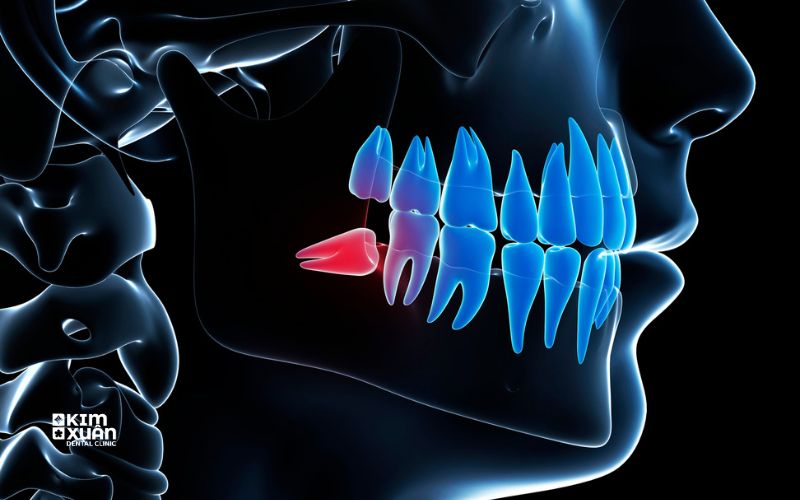

1. Răng Khôn Mọc Ngầm Là Gì?

Răng khôn, hay còn gọi là răng số 8, là chiếc răng mọc sau cùng trên cung hàm, thường xuất hiện trong độ tuổi từ 17 - 25. Khi xương hàm đã phát triển ổn định và không còn đủ khoảng trống, răng khôn rất dễ gặp tình trạng mọc bất thường.

Răng khôn được gọi là mọc ngầm khi:

Răng không thể trồi lên khỏi nướu

Bị kẹt hoàn toàn hoặc một phần trong xương hàm

Mọc lệch, mọc xiên hoặc đâm ngang về phía răng kế cận

Tình trạng này có thể xảy ra ở cả hàm trên và hàm dưới, tuy nhiên răng khôn mọc ngầm ở hàm dưới thường gặp hơn và dễ gây biến chứng hơn.